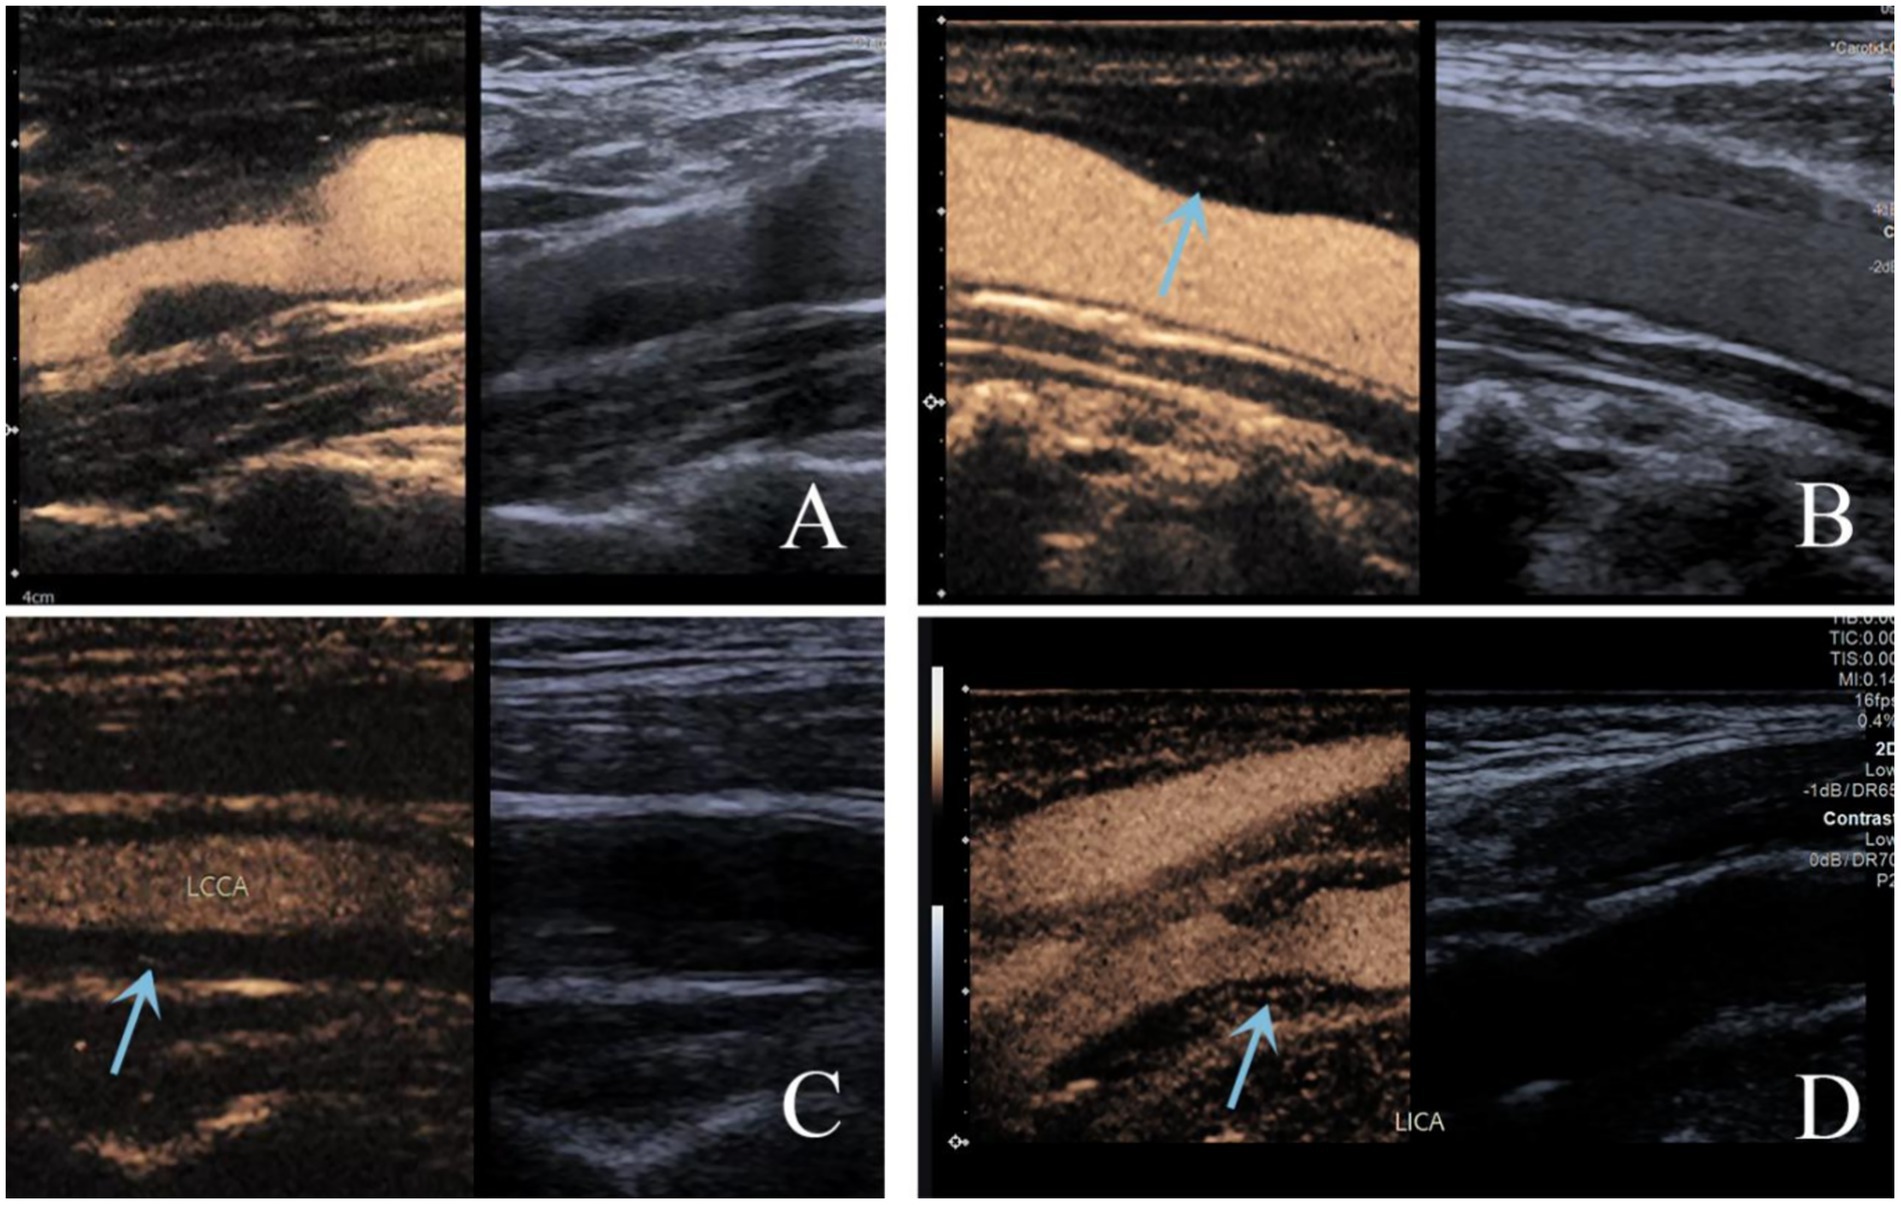

Ultrasound examinations were performed using a Siemens Acuson Sequoia color Doppler unit with an L9-3 probe. The contrast agent SonoVue (Bracco, Milan, Italy) was administered via an antecubital vein. Dynamic contrast-enhanced images were acquired to evaluate the distribution of the contrast agent within the plaque for CEUS classification. Plaques were classified as follows: Score 0: no intraplaque enhancement; score 1: punctate intraplaque enhancement; score 2: intermediate between scores 1–3, characterized punctate and 1–2 short linear of enhancement within the plaque; score 3: linear intraplaque enhancement penetrating or involving the majority of the plaque, or visible signs of blood flow (21) (Figure 1). Standardization and Blinding Procedures: Plaque grading was independently conducted by two senior ultrasound physicians with substantial CEUS expertise. Both examiners were blinded to the clinical data and group assignment. In the event of discrepancies, consensus was achieved via discussion. This ensured standardized plaque evaluation and minimized assessment bias. The inter-rater agreement for plaque grading between the two independent raters was assessed using the Kappa statistic, which yielded a value of 0.76 (95% CI 0.70–0.86), indicating good agreement between the raters.

Figure 1

Standardized grading criteria for the degree of contrast enhancement within plaques on ultrasound: A Score 0: no intraplaque enhancement; B score 1: punctate intraplaque enhancement; C score 2: intermediate between scores 1–3, characterized punctate and 1–2 short linear of enhancement within the plaque; D score 3: linear intraplaque enhancement, penetrating or involving the majority of the plaque, orvisible signs of blood flow.